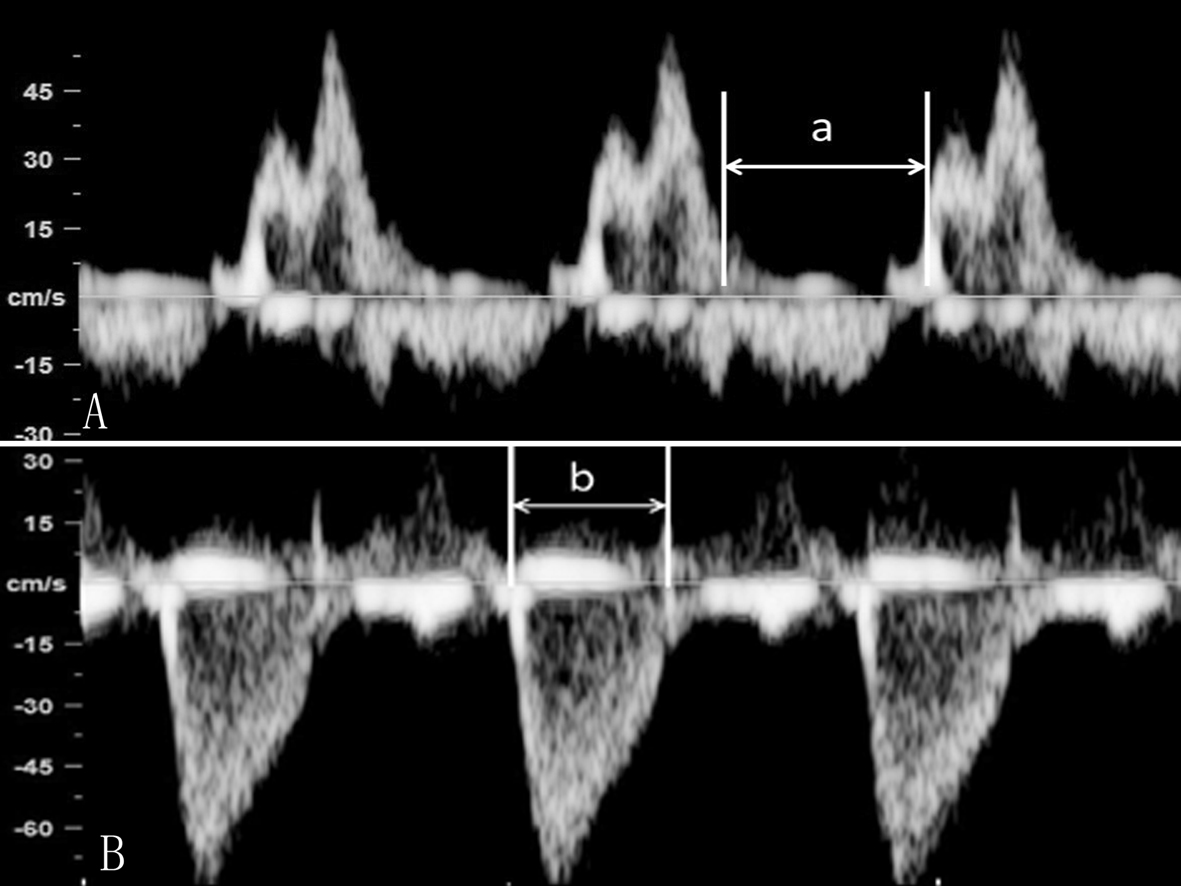

m型超声心动图法(motion echocardiography) 二维超声心动图法(too